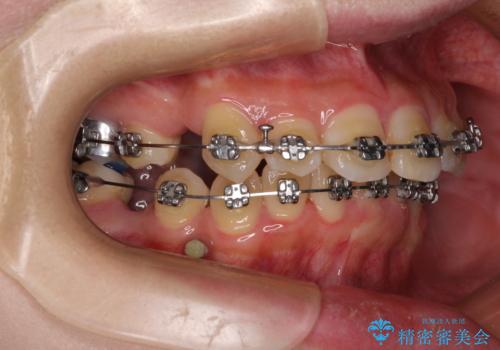

- 矯正装置

- メタルブラケット

- 上下の八重歯を気にして来院された患者様です。

非抜歯矯正で歯列を整えると、治療後に口元が今よりも突出する可能性が高かったため、上下左右の小臼歯4本を抜歯し、ワイヤー装置にて矯正治療を行うこととしました。

右上の八重歯の影響で、右側は上顎歯列が前方位の咬み合わせとなってしまっていたため、上顎は第一小臼歯を、下顎は第二小臼歯を抜歯することで咬み合わせや上下正中を調整することとしました。